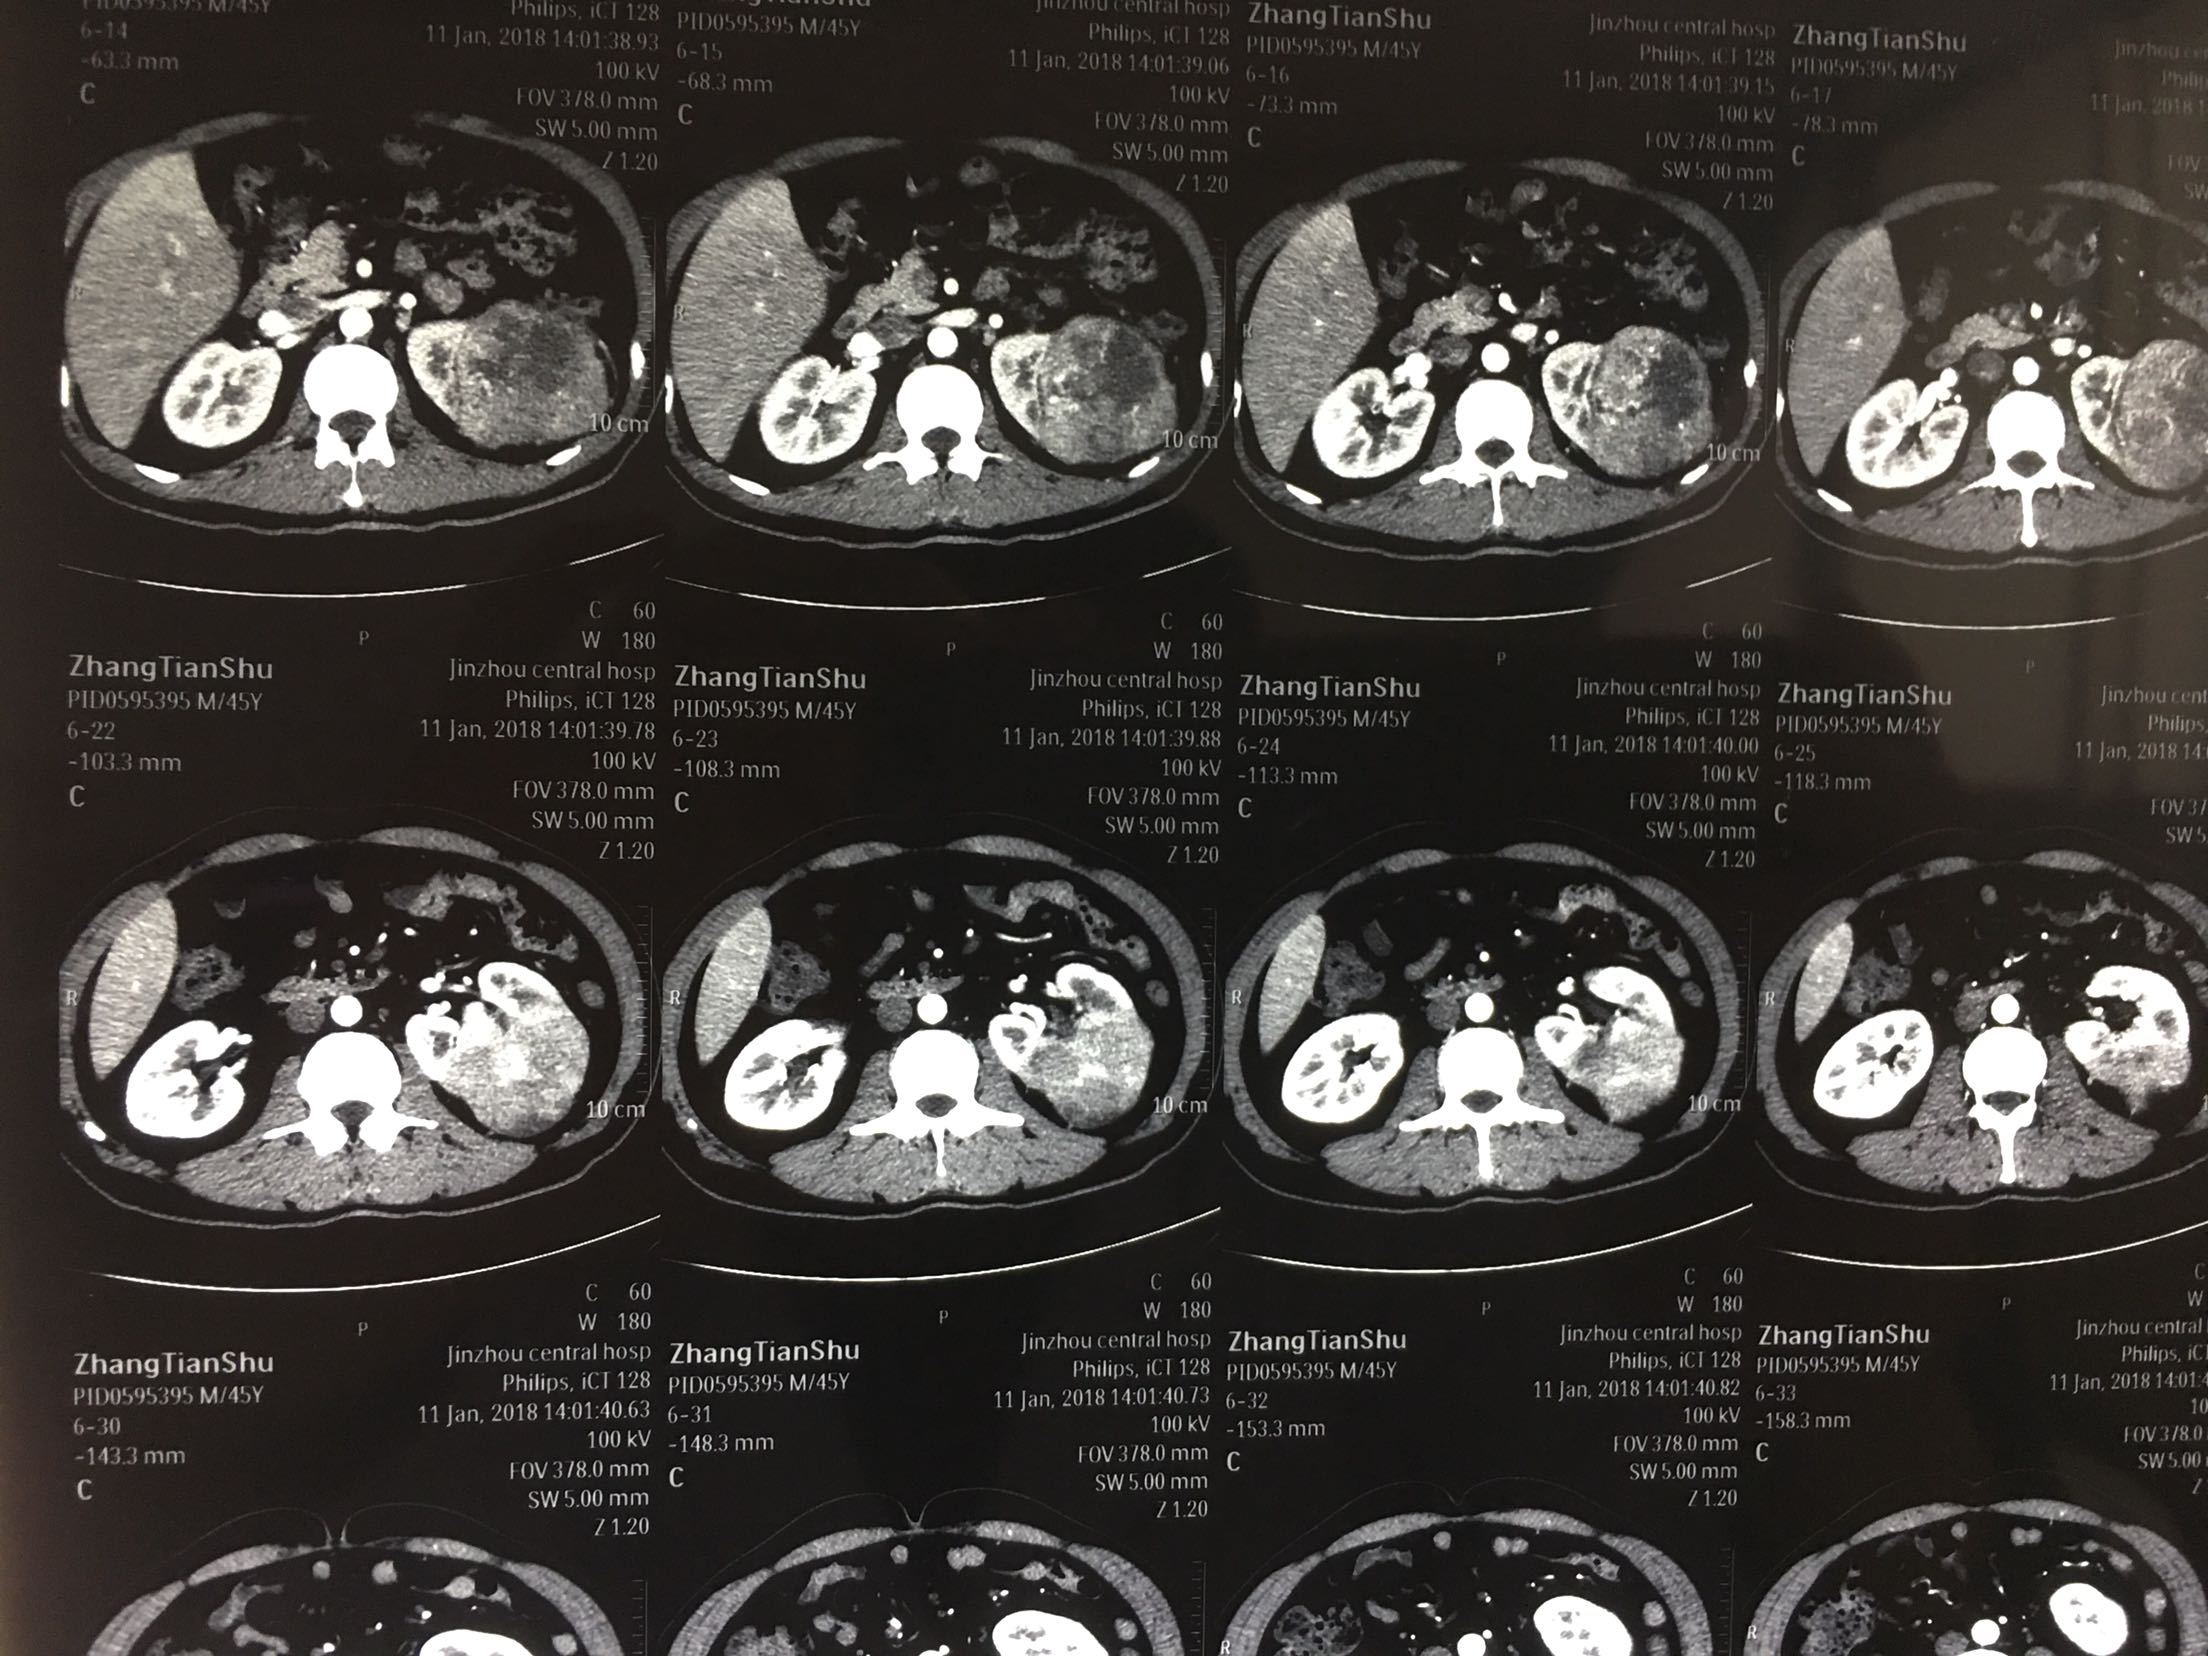

查体:左肾区轻叩击痛,双输尿管走形区无压痛,耻骨上区无隆起及压痛, 辅助检查:泌尿系彩超:左肾肿瘤。 ctu:左肾癌伴同侧肾上腺侵犯。

诊断:左肾癌伴肾上腺转移 治疗:根治性左肾切除术

术后病理:左肾透明细胞癌局部肉瘤样变,肾上腺及腹膜累及。 讨论:肾脏肿瘤肉眼血尿,腰疼,腹部包块为晚期肿瘤症状,预后不良。